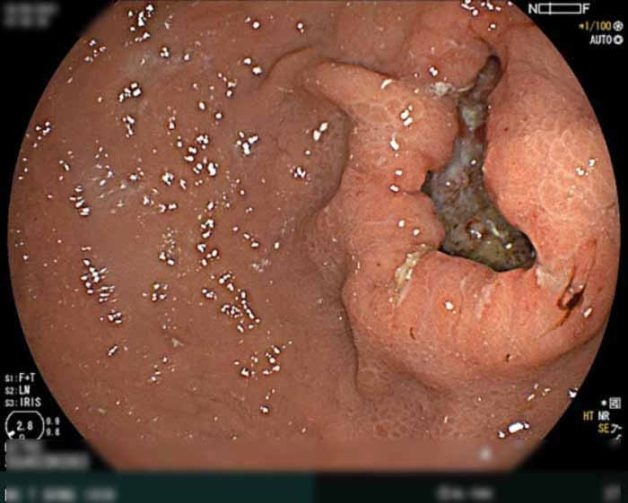

Hình ảnh nội soi ung thư dạ đày dạng loét type III